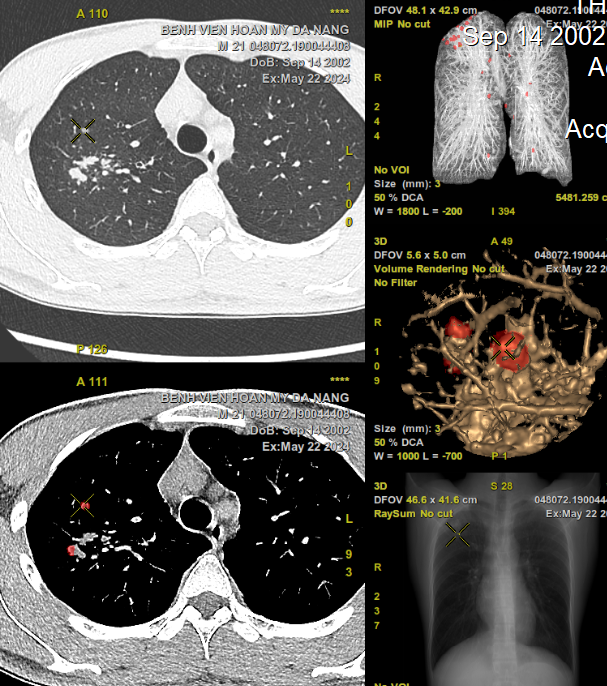

Bệnh viện Hoàn Mỹ Đà Nẵng vừa trang bi hệ thống chụp CT 256 lát cắt hai mức năng lượng ứng dụng trí tuệ nhân tạo (AI) có khả năng phát hiện các nốt phổi nhỏ kích thước cỡ 2 mm. Kết quả được lọc và đọc tự động, bác sĩ sẽ dễ dàng sàng lọc những tổn thương nghi ngờ. Làm gia tăng tính chính xác, hạn chế bỏ sót tổn thương, tiết kiệm thời gian và nâng cao hiệu quả điều trị kịp thời cho người bệnh. Nhờ khả năng chẩn đoán sớm mà các bác sĩ có chiến lược điều trị phù hợp hoặc phẫu thuật cắt bỏ các khối u ác tính khi còn nhỏ, giúp nâng cao cơ hội sống cho người bệnh.

Hình ảnh CT 256 lát cắt phổi hiện đại có ứng dụng trí tuệ nhân tạo (AI) giúp phát hiện gần như tất cả các tổn thương dù có kích thước nhỏ

Bác sĩ Biện Văn Thiện, Trưởng khoa Chẩn đoán Bệnh viện Đa khoa Hoàn Mỹ Đà Nẵng cho biết: Chụp CT phổi hai mức năng lượng có ứng dụng AI là một kĩ thuật hiện đại bậc nhất hiện nay. Đây là kỹ thuật không xâm lấn, không gây đau đớn, sử dụng tia X liều thấp để tầm soát ung thư phổi. Kỹ thuật này giúp các bác sĩ nhìn thấy các tổn thương một cách chính xác, hạn chế bỏ sót. Đối với người bình thường, chụp CT phổi giúp phát hiện những dấu hiệu ung thư phổi như các nốt nhỏ, khối u nhỏ. Đối với những người có nguy cơ cao sẽ được thực hiện kỹ thuật chụp CT phổi liều thấp, kỹ thuật này có thể giúp tìm ra mầm mống của ung thư tốt hơn nhiều so với chụp X-quang phổi thường qui. Chỉ định chụp CT ngực liều thấp để tầm soát định kỳ hàng năm cũng là điều cần thiết. Đặc biệt với máy CT 256 lát cắt hai mức năng lượng ứng dụng AI, đây là thế hệ máy mới nhất, được xem như là hiện đại và hiệu quả bật nhất hiện nay.